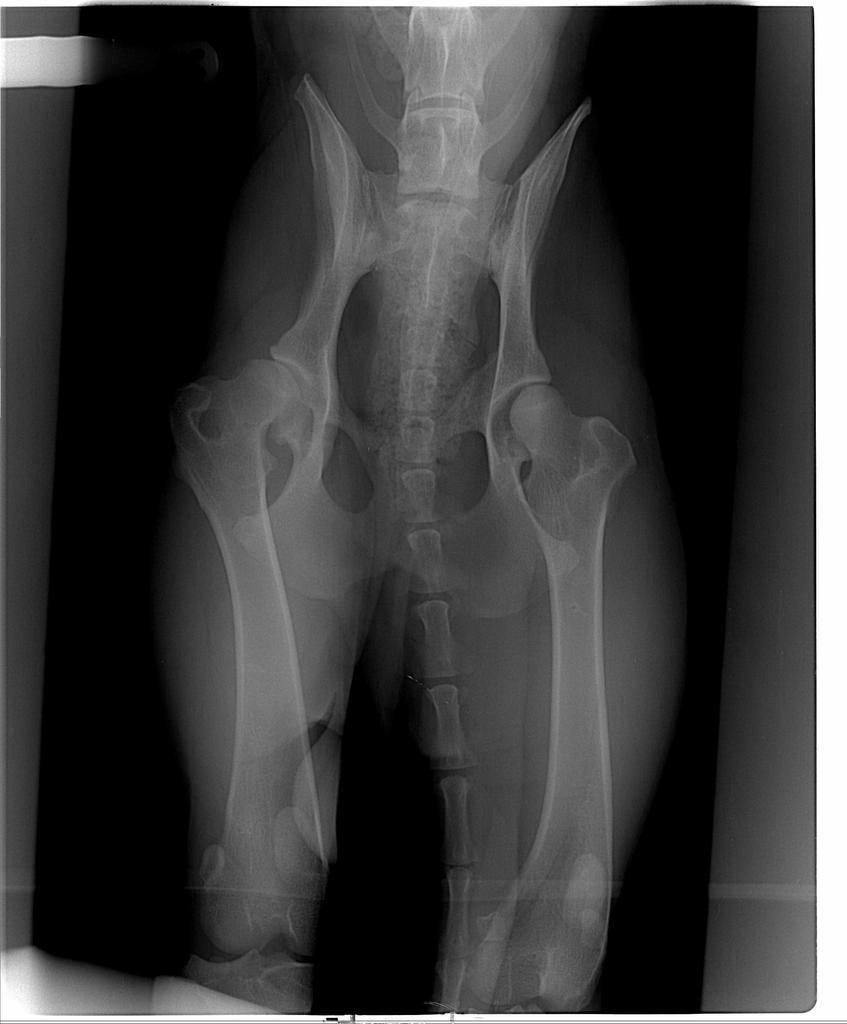

ewula Posted November 20, 2008 Author Posted November 20, 2008 Jesteśmy "po", ale niestety jednak o TPO trzeba było zapomnieć :shake: - zbyt mała miednica, kość trzebaby pod jakims nienaturalnym kątem ustawiać co mogłoby być dyskomfortem podczas poruszania się , wręcz krzywdą dla pieska - najogólniej chodzi o to ze mógłby mieć tę łape tylko w jednej pozycji, tzn. prosto a w bok nie mógłby jej podnieść, np. przy siusianiu. Więc niestety ta metoda odpadła, można było to stwierdzic dopiero przy badaniu go juz po uspieniu. Była więc obustronna daroplastyka, mam nadzieję że wszystko dobrze, choć na to prawe biodro to było ryzyko. Jestem w domu, po 20 mam dzwonić. Zostawiłam go w klinice, lekarz stwierdził że to doskonały pomysł, że go nie zabieramy tak szybko. Ale pewnie w sobotę po niego pojedziemy, z tęsknoty... Odezwe się po 23 albo dopiero jutro rano... Dzięki za trzymanie kciuków :loveu: Quote

AgaCzarna Posted November 26, 2008 Posted November 26, 2008 Bracia wrocili z Wroclawia...specjalista wypowiedzial sie,ze wada jest bardzo powazna zwlaszcza 1 biodra,ktore nie nadaje sie na operacje...za plytka panewka i juz zaczelo robic sie zwyrodnienie...Moze byc tak,ze za pol roku w ogole przestanie chodzic...juz teraz go bardzo boli...Niestety pozostaje tylko uspienie:-(:-(:-(:-(:-( 3mam kciuki za tych ktorym sie udalo Quote